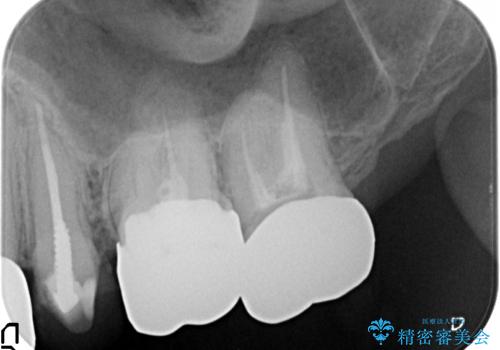

- 「虫歯が多発し、治療が終わらない。歯も無くなったし今後悪くならないような治療をしたい。」と精密治療を希望され来院されました。

虫歯の徹底的な除去やセラミック補綴、精密根管治療、歯周外科を行うことで、治療後に歯磨きがしやすく、かみやすい機能的な仕上がりへと導きます。

歯周外科手術をおこなったことでフェルールも獲得でき、破折リスクをより抑えることにも成功しています。